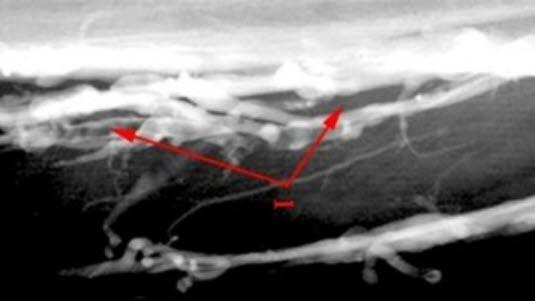

Ved venografi kan man finne fersk blodpropp f.eks. ved undersøkelse av venene i leggen. Man kan også se unormal fyllningsgrad av sidegrener til venen man undersøker, noe som tyder på manglende fylling av venen. Dette funnet er vanskelig å tolke.